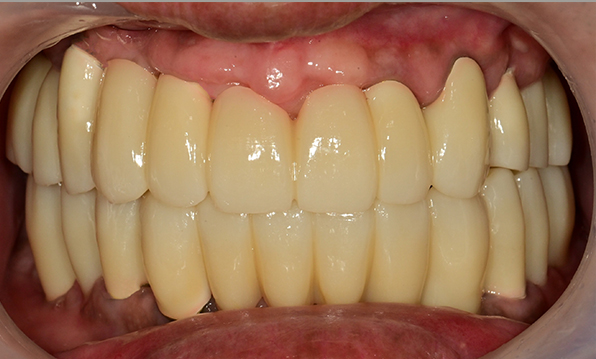

전체 임플란트

위 아래 치아가 정확하게 맞아야하는 고난이도 임플란트

임상 경험이 많은 숙련된 전문의의 섬세한 기술력이 중요합니다.

치료기간 : 2021.04.12~2021.09.15